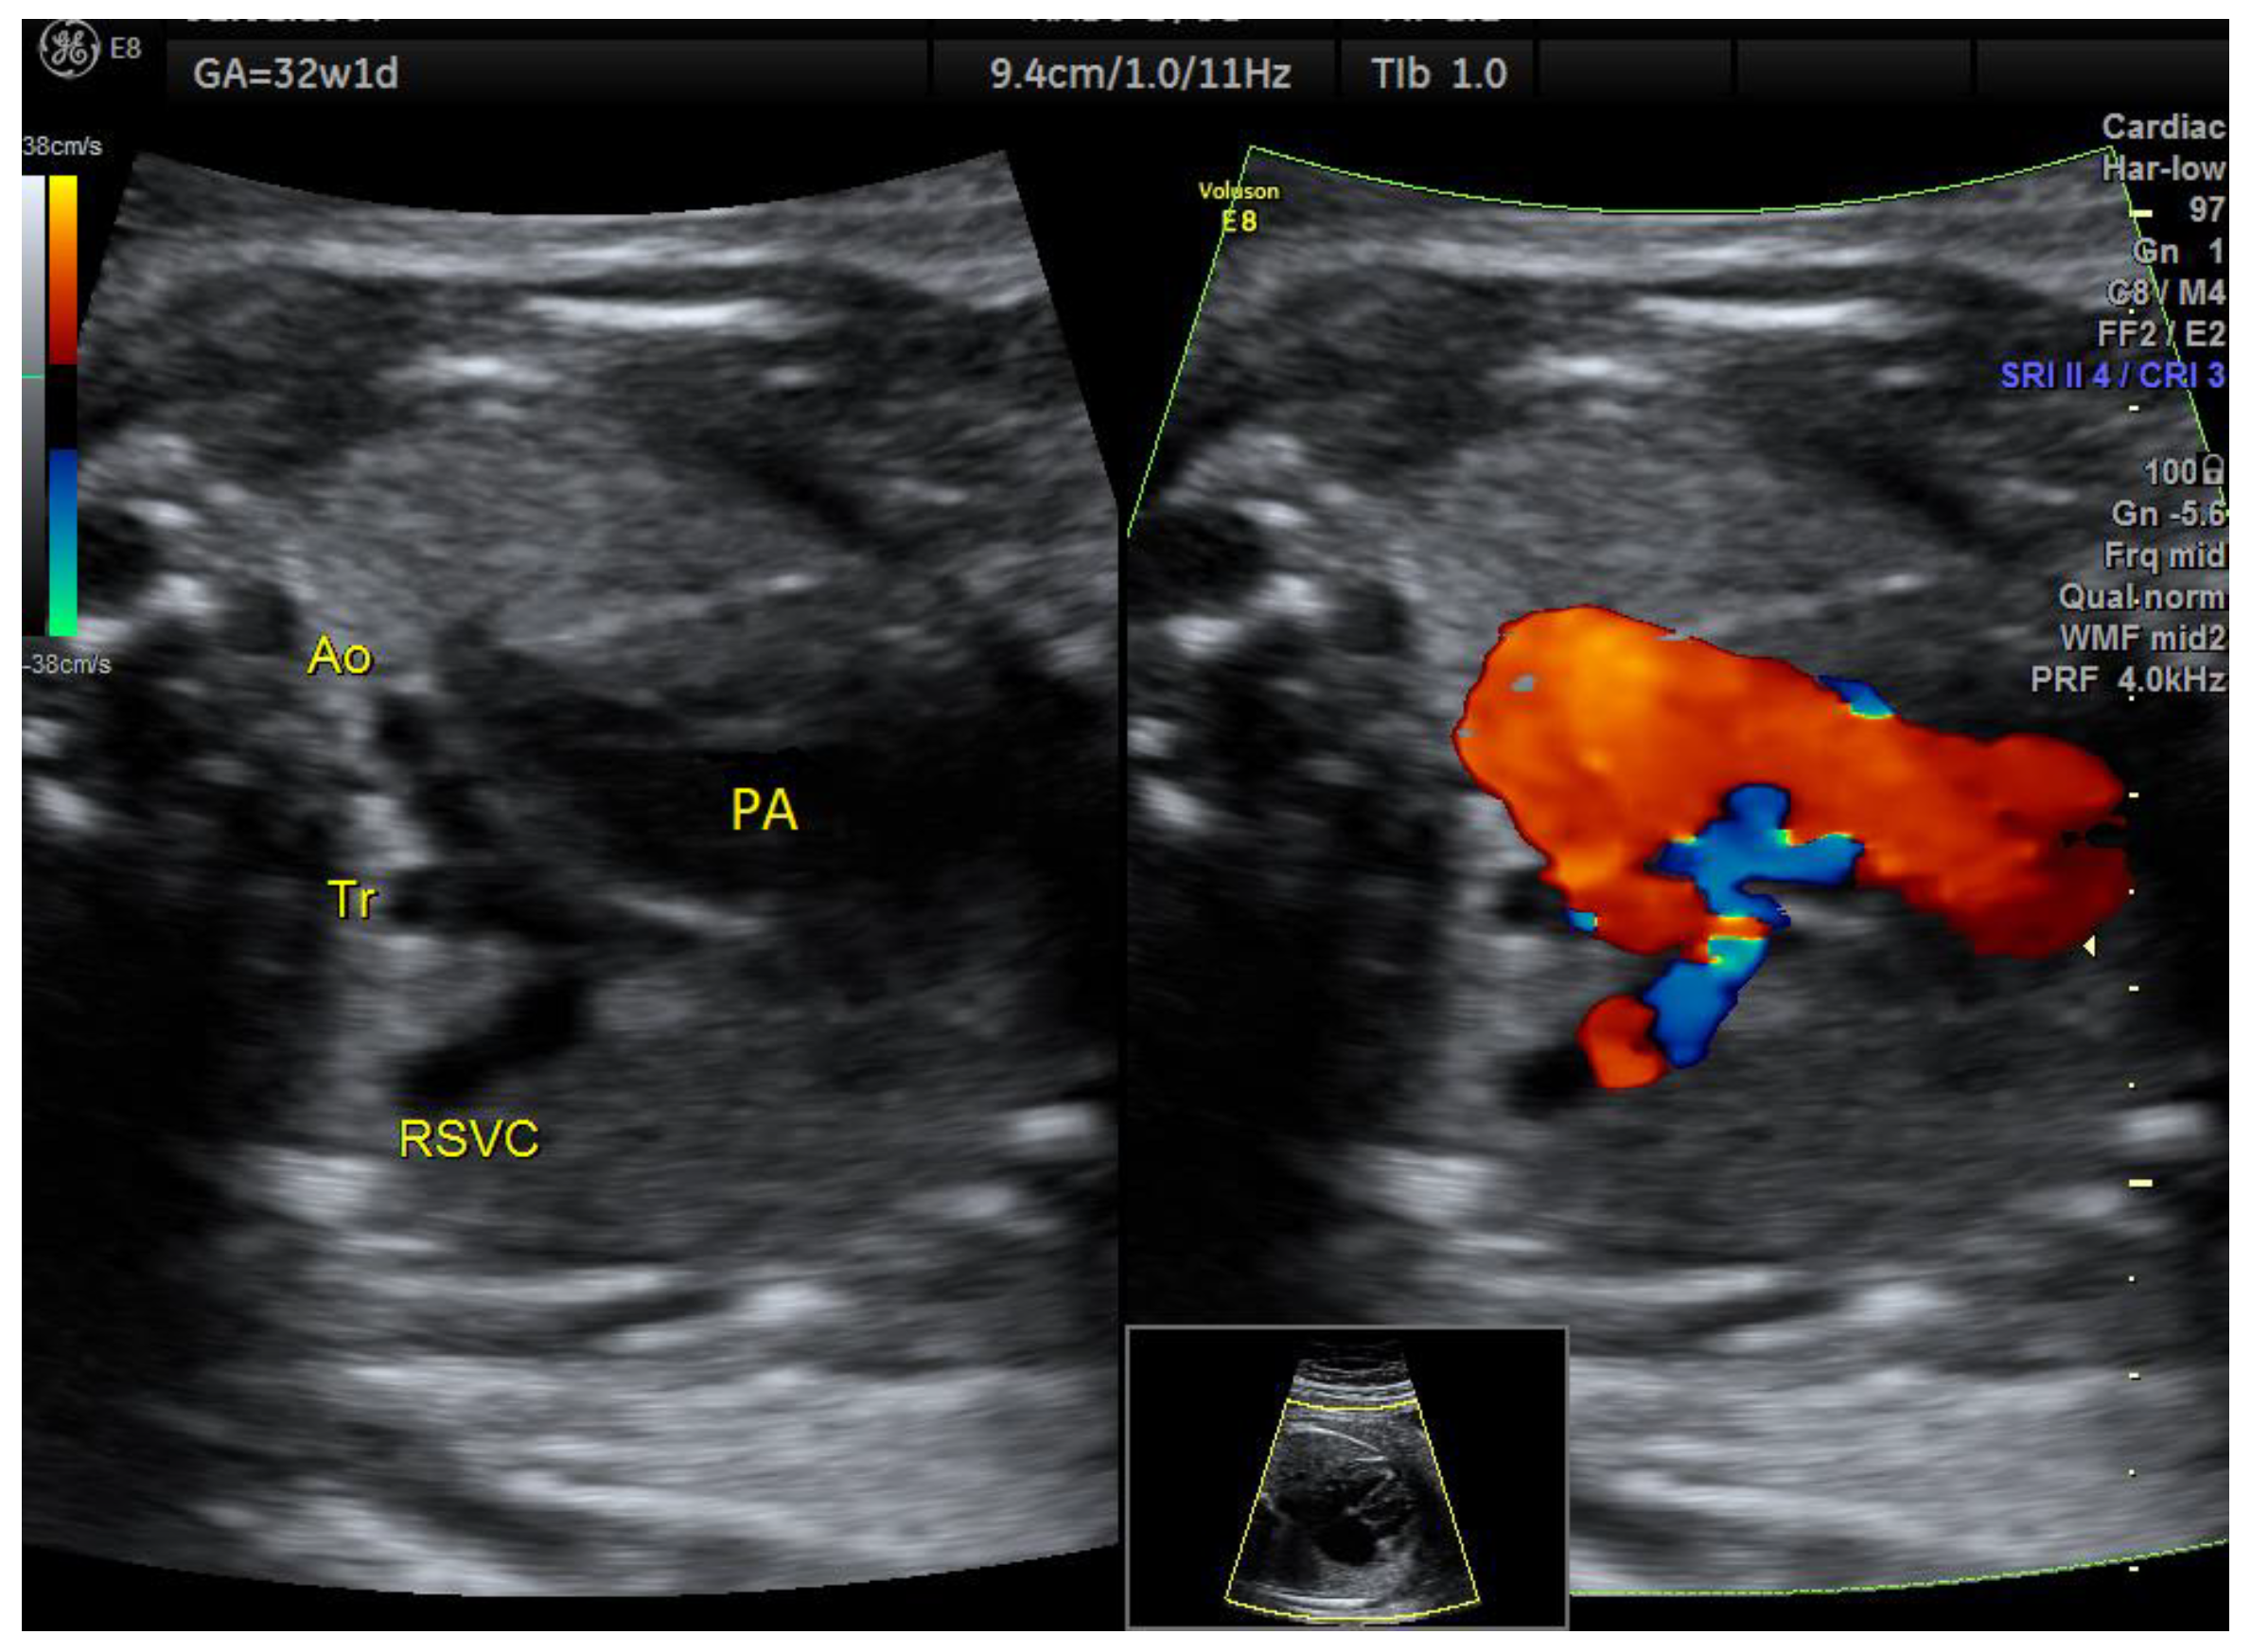

| Aortic coarctation | 3 | 1 × (hypoplastic NB and late FGR) | - | 3VT | + | 0 | 2 | 1 | 2/3 |

| IAoA | 1 | perimembranous VSD | - | 3VT | + | 0 | 1 | 0 | 1/1 |

| Fallot | 1 | - | - | 3VT | + | 0 | 1 | 0 | 1/1 |

| RAA | 1 | - | perimembranous VSD | 3VT | + | 1 | 0 | 0 | 1/1 |

| D-transposition 3 | 1 | - | - | 3VT | + | 0 | 0 | 1 | 1/1 |